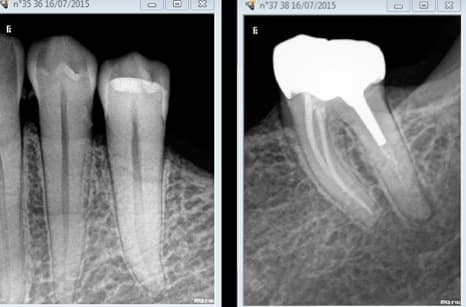

Ca m'énerve des bridges j'en fait très peu, je supporte pas étonnant de ma part, non ? -)))

En plus j'aurais du faire un RTE sur 37, mais ca commence à me gaver les RTE j'arrete pas. Et puis il faut bien que j'en laisse à mon successeur un de ces 4. -)))

Ce patient était demandeur ( un peu moins maintenant lol !) pour bénéficier des avancées de la CCAM pour un bridge 35 37, je fais quoi ? je lui en fait profiter ? -))))

Merde encore un RTE. -)))